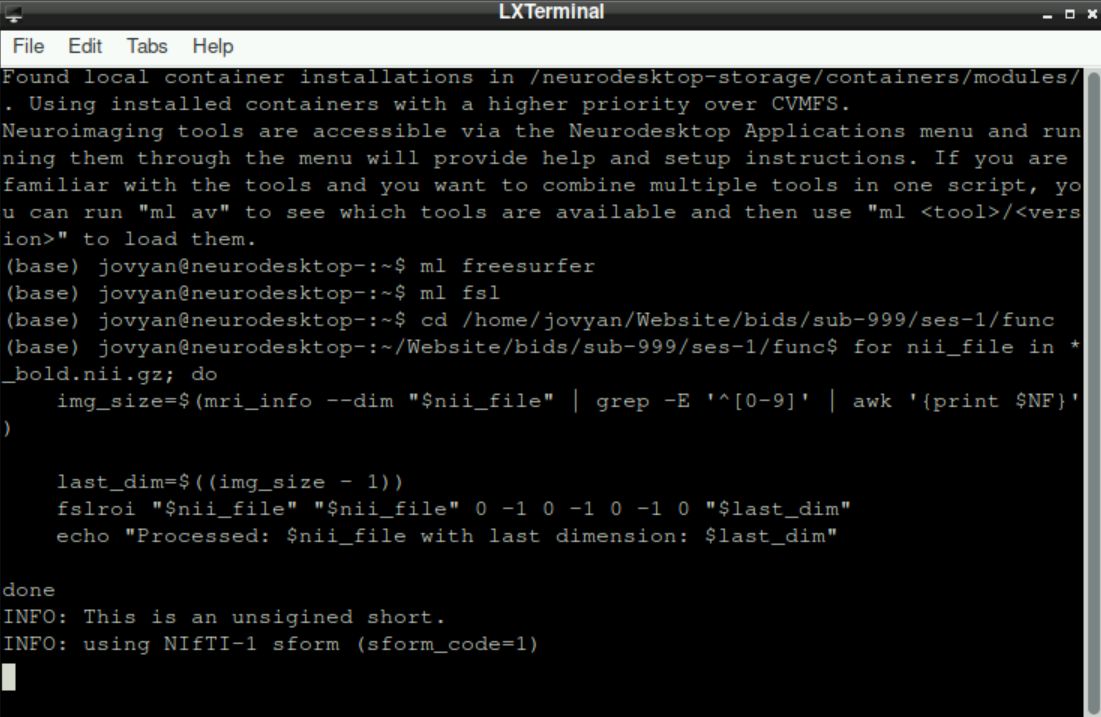

ml freesurferand press enterType

ml fsland press enterSet your working directory to the directory with your functional data (i.e. the

funcdirectory in your BIDS-structure). For this, typecdfollowed by a space and then the path to the directory (type it in, or copy/paste approach described here). In the example below, the complete line iscd /home/jovyan/Website/bids/sub-999/ses-1/func

The additional paths on the left of your cursor indicate, that the change of working directory was successfull:

- Now we have to remove the last frame from each nifti file, since the last frame is the denoising. For this, copy paste the following code:

for nii_file in *_bold.nii.gz; do

img_size=$(mri_info --dim "$nii_file" | grep -E '^[0-9]' | awk '{print $NF}')

last_dim=$((img_size - 1))

fslroi "$nii_file" "$nii_file" 0 -1 0 -1 0 -1 0 "$last_dim"

echo "Processed: $nii_file with last dimension: $last_dim"

doneInformation: this code basically searches for all files in your working directory that end on _bold.nii.gz, gets the information about how many frames it includes using mri_info and then removes the last frame (which we confirmed to be the denoising scan prior)

When you copy/paste into the terminal, the line breaks and indentation probably will look different, but this is no problem (see image below). Press enter to execute the pasted code.